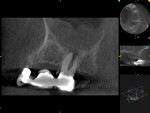

The patient underwent a CBCT study (Kodak 9000, Carestream Dental, carestreamdental.com) for further evaluation of the area (Figure 2). The 3D scan revealed thickening of the mucous membrane of the maxillary sinus, indicating severe chronic sinusitis and a large periradicular radiolucency at the apices of No. 14 (Figure 2). The pulpal diagnosis of tooth No. 14 was necrotic and the periapical diagnosis was chronic apical periodontitis.